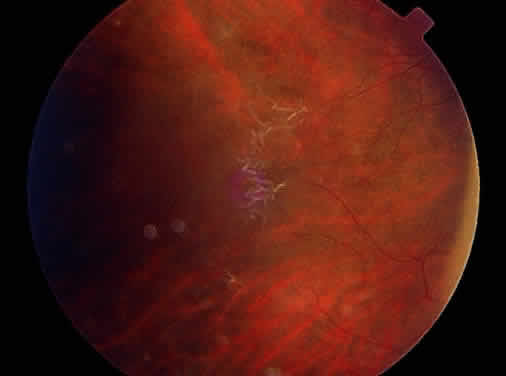

Clinically, retinal schisis presents with decreased central visual acuity, absolute scotomas, or both.1,33,38 Children may have strabismus and nystagmus.25,47 As in FEVR, but in contrast to Wagner and Stickler syndrome, the refraction tends to be hypermetropic (“hypermetropic amblyopia”).1,25,26,31–34,40,48 On biomicroscopic examination, edema and cystic central macular schisis of the retina are apparent in virtually all cases.37,38 Loss of macular reflex, which may be an early sign,34,35 is followed by wheel-like formation,37 a multicystic radiate appearance (Fig. 1),38 pigmentary degeneration, and cystic macular atrophy (Fig. 2).38 These macular changes, not bullous schisis per se, determine visual loss in patients often in the fourth or fifth decade of life.51

Peripheral retinal schisis is present in half of the patients and in 96% is located in the inferotemporal quadrant.48 At least initially, the inner layer of the schisis is attached to the vitreous and features vessels, internal limiting membrane, and nerve fiber layer. These tissues undergo progressive atrophy as well as reactive gliosis, which in a perivascular location may appear as vascular sheathing (Fig. 3). Total atrophy may result in dehiscences and peripheral arborization of the retinal vasculature.33,34,45 Optic atrophy may follow.40 The outer layer of the schisis cavity also undergoes atrophy, reactive gliosis, intralayer pigment migration, and hole formation. A rhegmatogenous detachment may be the sequela in 4% to 22% of all patients.30,42,49,51–53 With time, the vitreous undergoes syneresis and detachment.31,33,40 Vitreous detachment actually may improve the schisis by releasing traction. Adhesions to retinal vessels are responsible for frequently found vitreous hemorrhages.29,31,40